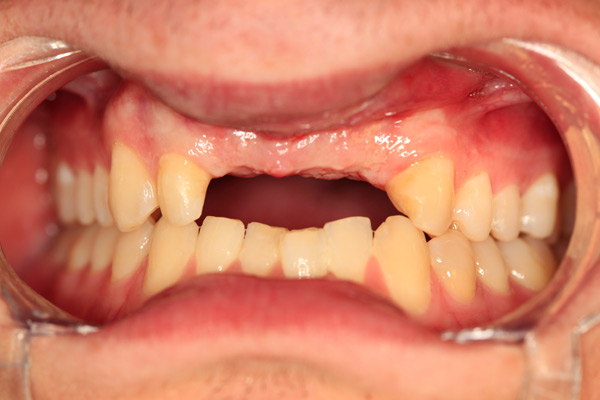

Problem: This patient presented with severe decay and a difficult occlusion/bite. He had teeth that had already been removed.

Plan: Our plan… remove the rest of the teeth and place an upper denture. Place four implants on the lower using guided surgery. Restore with a fixed/hybrid bridge.

A solution to every problem.